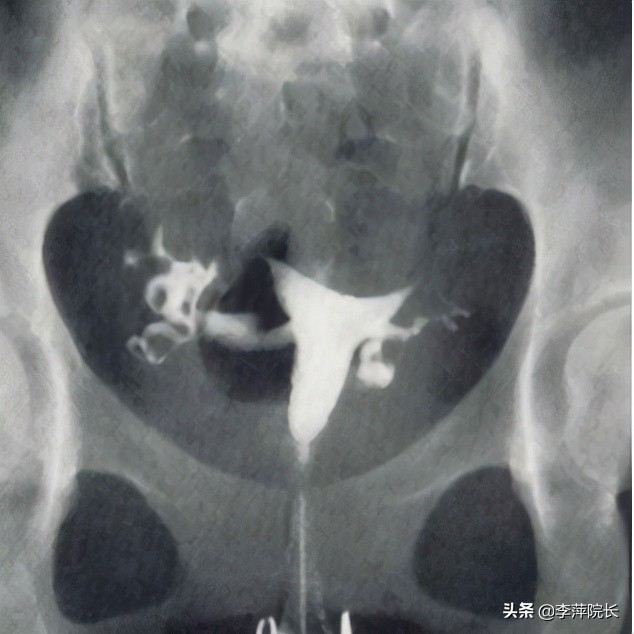

说罢,我让护士带她去做了基本检查,排除其他不孕的因素之后,利用输卵管造影,发现输卵管远端有膜性粘连,引发了轻度伞端闭锁。为了避免输卵管痉挛造成假性不同的结果,肌注阿托品以防万一。之后我利用宫腔镜观察,输卵管的疏通情况,通液注入,发现输卵管是通畅的,只需要分离远端的轻度粘连即可,无需额外的手术。